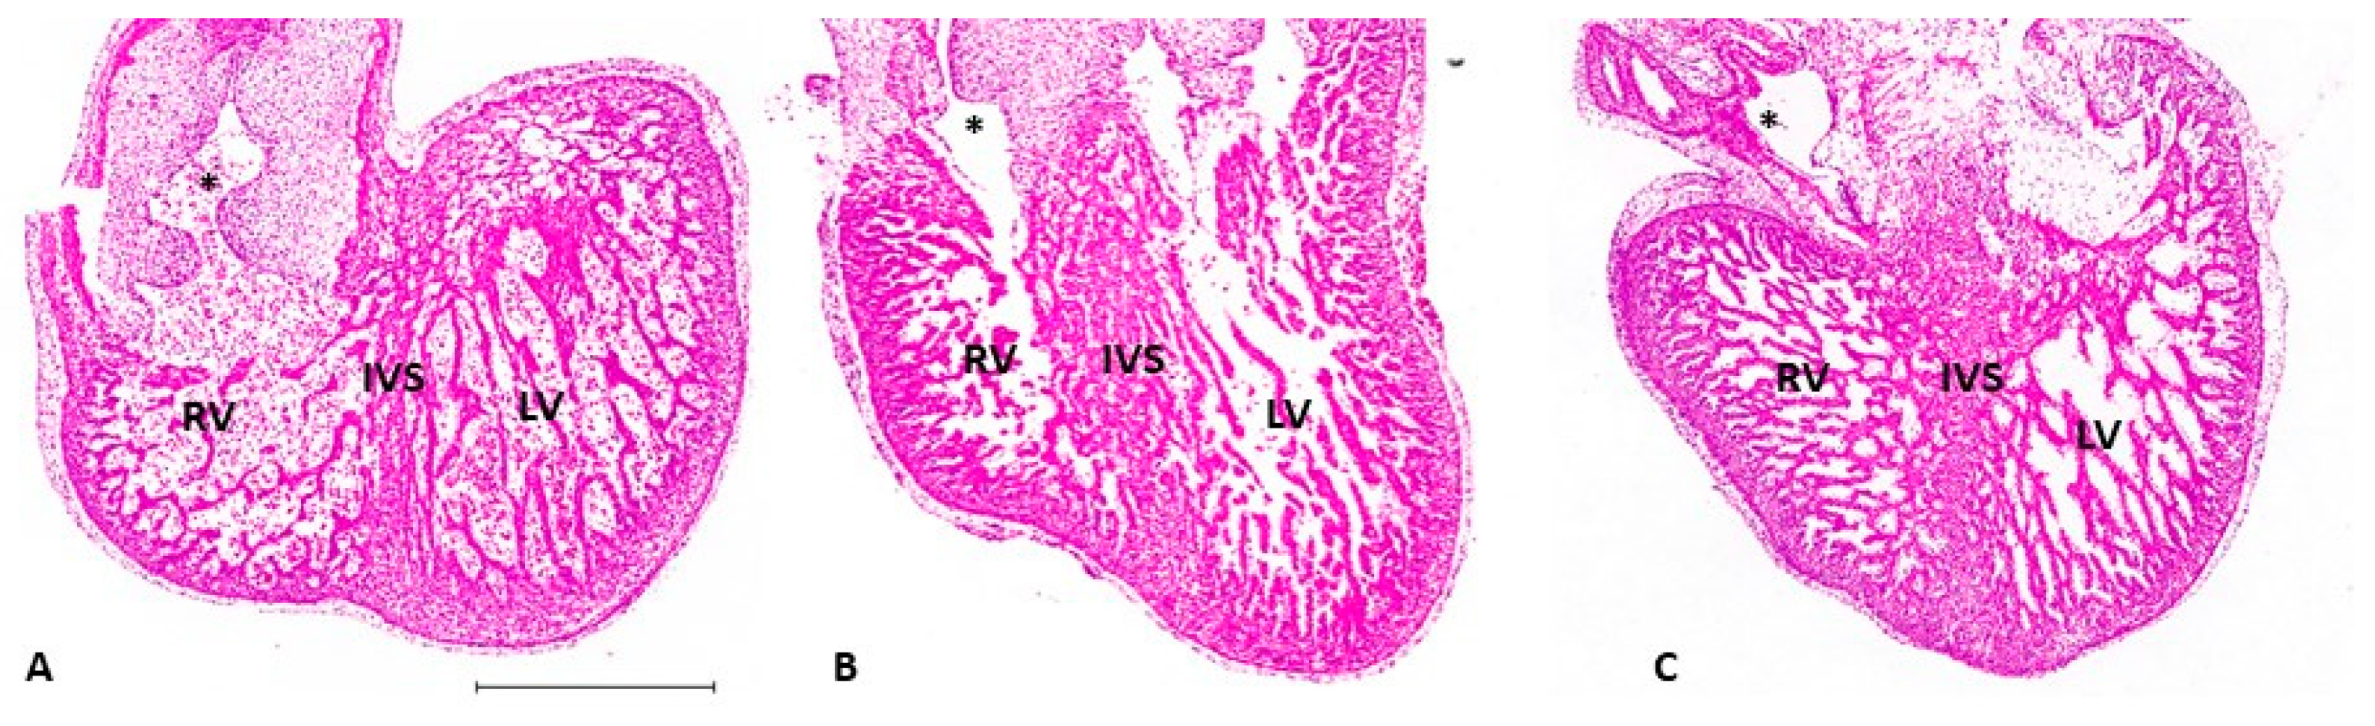

5.2. Ventricular Formation

5.3. Outflow Tract and Great Vessels